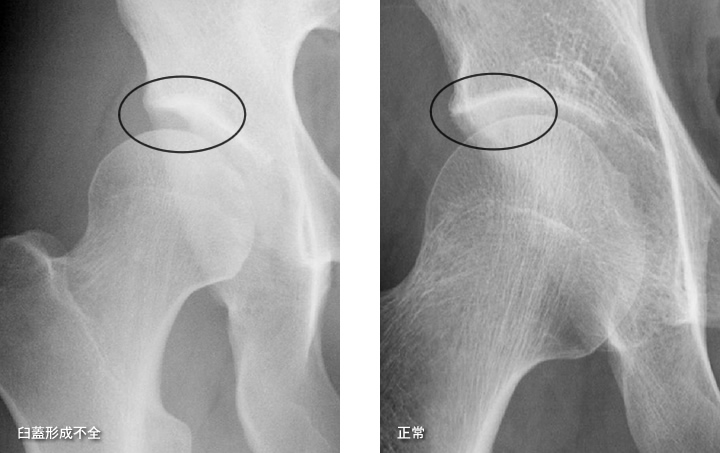

② 臼蓋形成不全(きゅうがいけいせいふぜん)

股関節の受け皿が浅いため、骨頭をしっかり支えられず、関節に負担が集中します。

特に日本人女性に多く、40〜50代で症状が出るケースが増えています。